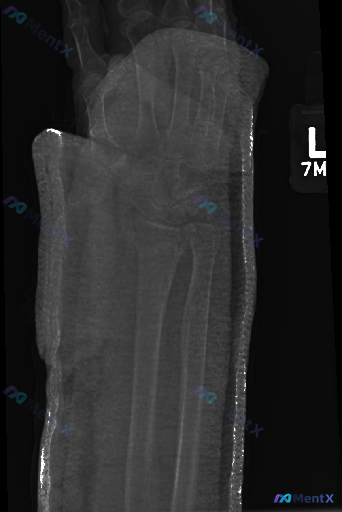

这张左侧腕部CT定位像,你能观察到哪些值得注意的异常?

整理到一张左侧(L)腕关节及前臂的CT定位像资料,和大家讨论一下读片思路。

- 成像类型:CT定位像(Scout View/Topogram)

- 成像部位:左侧腕关节及前臂

- 骨骼结构:低分辨率下可见桡骨、尺骨及其远端,以及腕骨区域的大致轮廓;桡骨远端和尺骨茎突的轮廓尚保持连续性,未见明显的骨皮质中断、移位或明确的骨折线。

- 关节对位:桡腕关节及腕骨之间的排列关系大致正常,未见明显的关节脱位或半脱位征象,关节间隙未见明显的异常增宽或狭窄。

- 骨质密度:骨质密度分布均匀,未见明显的异常高密度影或明确的透亮区,皮质边缘平滑,无异常骨膜反应。

- 其他:图像边缘可见明显的高密度影,考虑为外固定表现;受外固定物遮挡及定位像对比度限制,无法准确评估软组织情况。